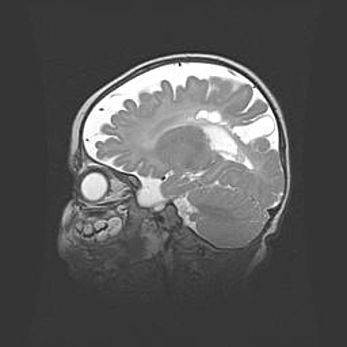

Сообщающаяся гидроцефалия. Кистозная энцефаломаляция головного мозга.

Возраст: 3 месяца 4 дня

Вес: 3100 г

Пол: женский

Окружность головы: 34 см

Срок гестации: 31 неделя

Кистозная энцефаломаляция головного мозга - одна из форм поражения головного мозга в детском возрасте. Характеризуется возникновением множественных и распространённых кист в коре, белом веществе и подкорковых образованиях головного мозга у плодов, новорождённых и детей раннего возраста. Развитие кистозной энцефаломаляции связано с внутриутробной асфиксией и гипотонией, родовой травмой, тромбозом синусов, пороками развития сосудов, инфекциями, сепсисом и другими причинами. Наиболее значимые инфекционные агенты: вирусы простого герпеса, цитомегалии, краснухи, токсоплазмы, энтеробактерии, золотистый стафилококк и другие.